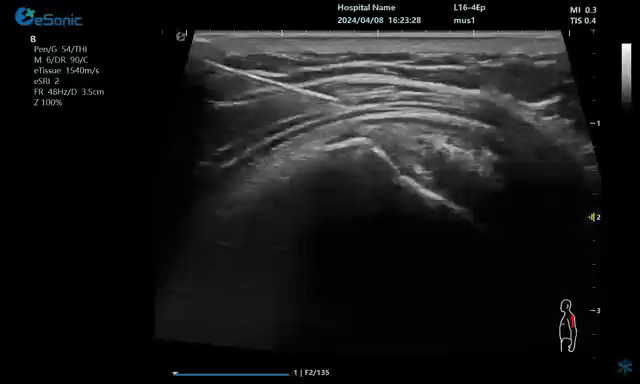

病例:冈上肌肌腱钙化穿刺治疗

640.gif

注射麻醉药

无磁导航技术引导穿刺钙化点